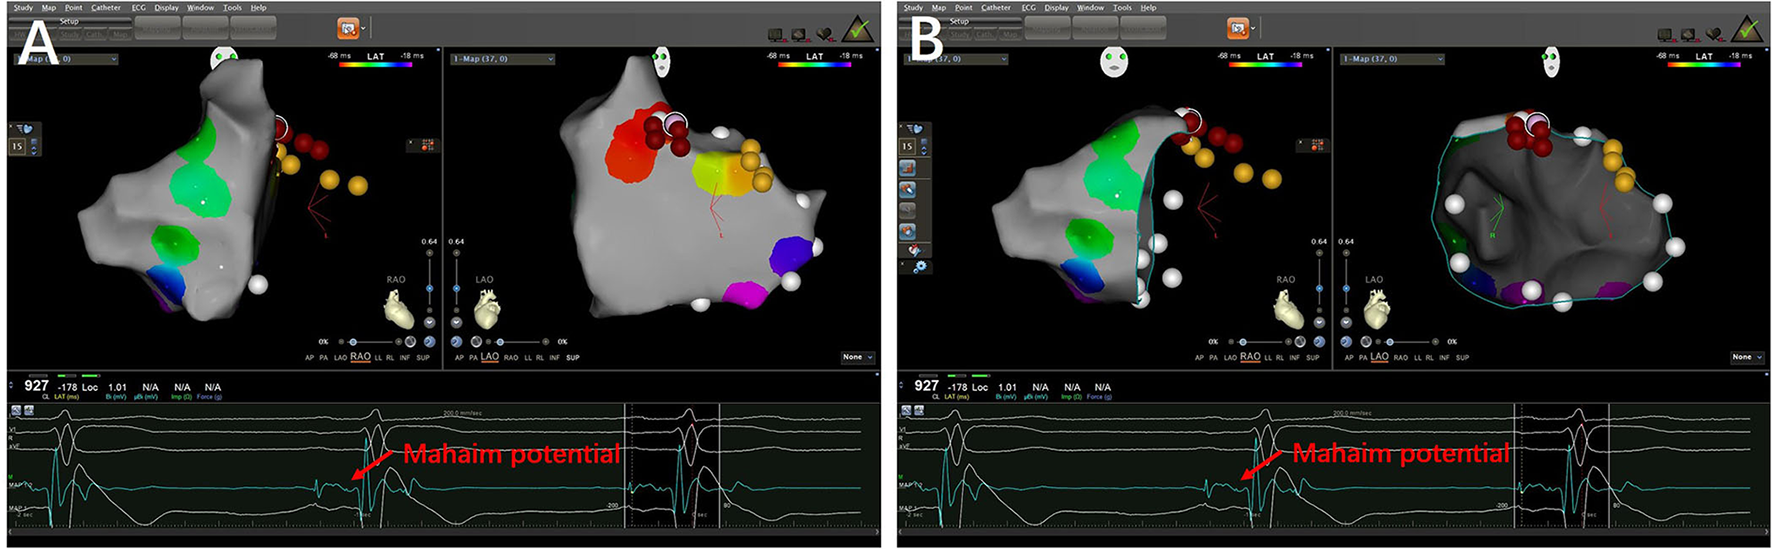

Figure 3

3-D mapping images of successful ablation sites in a patient with right-sided MAP. (A) The targets of Mahaim fiber located at the right anterior wall of tricuspid annulus (12:00 p.m.). (B) The target in ablated catheter presented Mahaim potentials.

RF ablation

After MAP was confirmed by the EP properties, a catheter (8 Fr, 3.5-mm-tip electrode, DD or JJ curve, 1-6-2 mm spacing, 115 insertion length, Thermocool SmartTouch SF® Biosense Webster Co.; or EPS, HT-Viewer system) was used for mapping and ablation. The MAPs were ablated with a target contact force of 10–15 g, a target ablation index (AI) of 500–600 watts/grams/second, and an impedance drop of 5–10 Ω. The tricuspid annulus and mitral annulus were mapped during sinus rhythm. For the left-sided MAPs, the transseptal approach was performed. The M potential was detected between atrial and ventricular intracardiac potential during sinus rhythm (Figure 3). The AM interval (between the beginning of the atrial electrogram and the M potential) and MV interval (between the M potential and the beginning of the ventricular electrogram) were recorded. The M potential was recorded at the atrial insertion site of the Mahaim fibers. It was considered a good predictor of a suitable ablation site (8). Successful ablation includes no ventricular pre-excitation, no AP conduction, and no inducible tachycardia observed during repeated programmed stimulation.